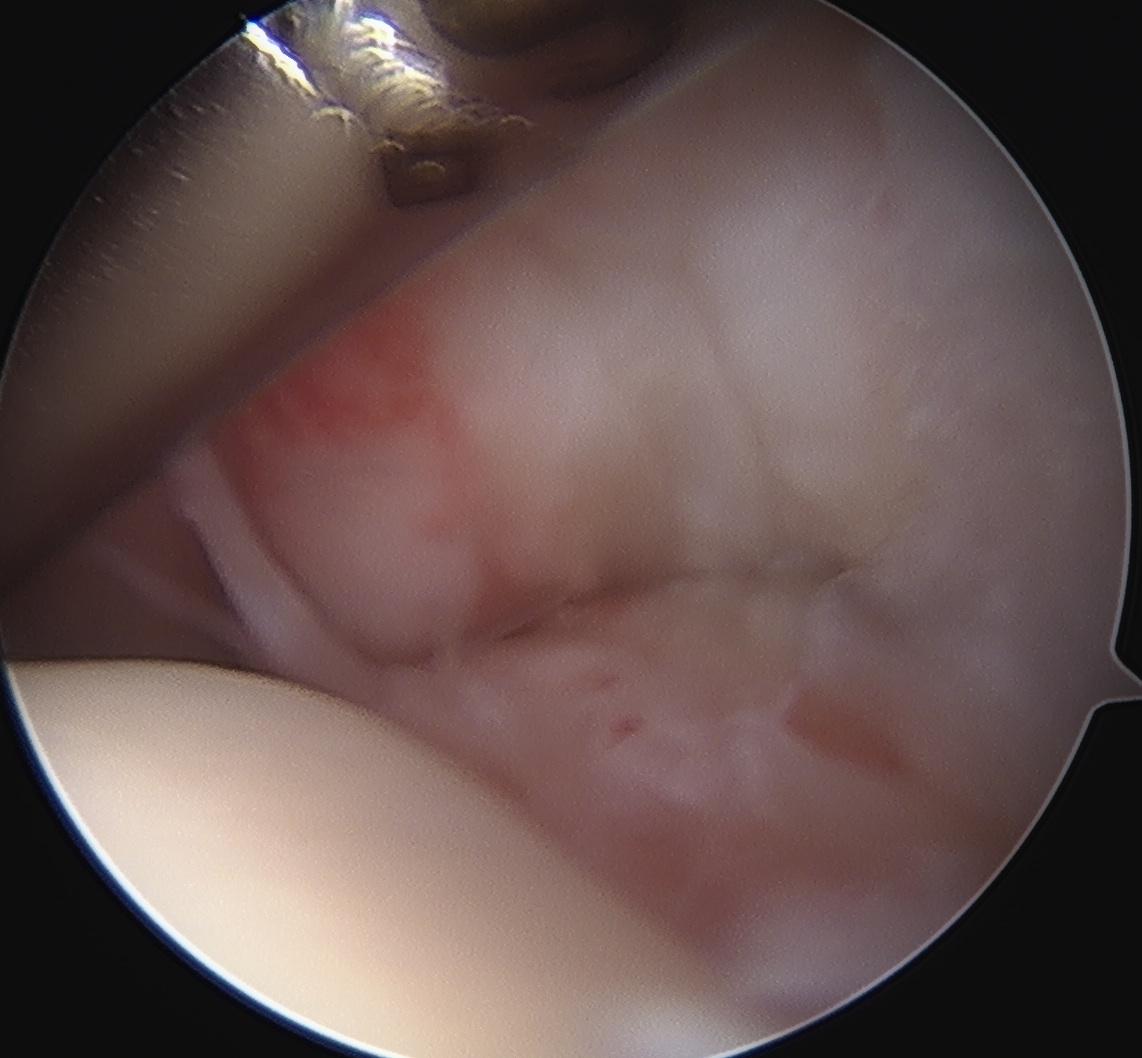

Articular side

Normal insertion of undersurface of the rotator cuff onto the footprint, with camera in glenohumeral joint